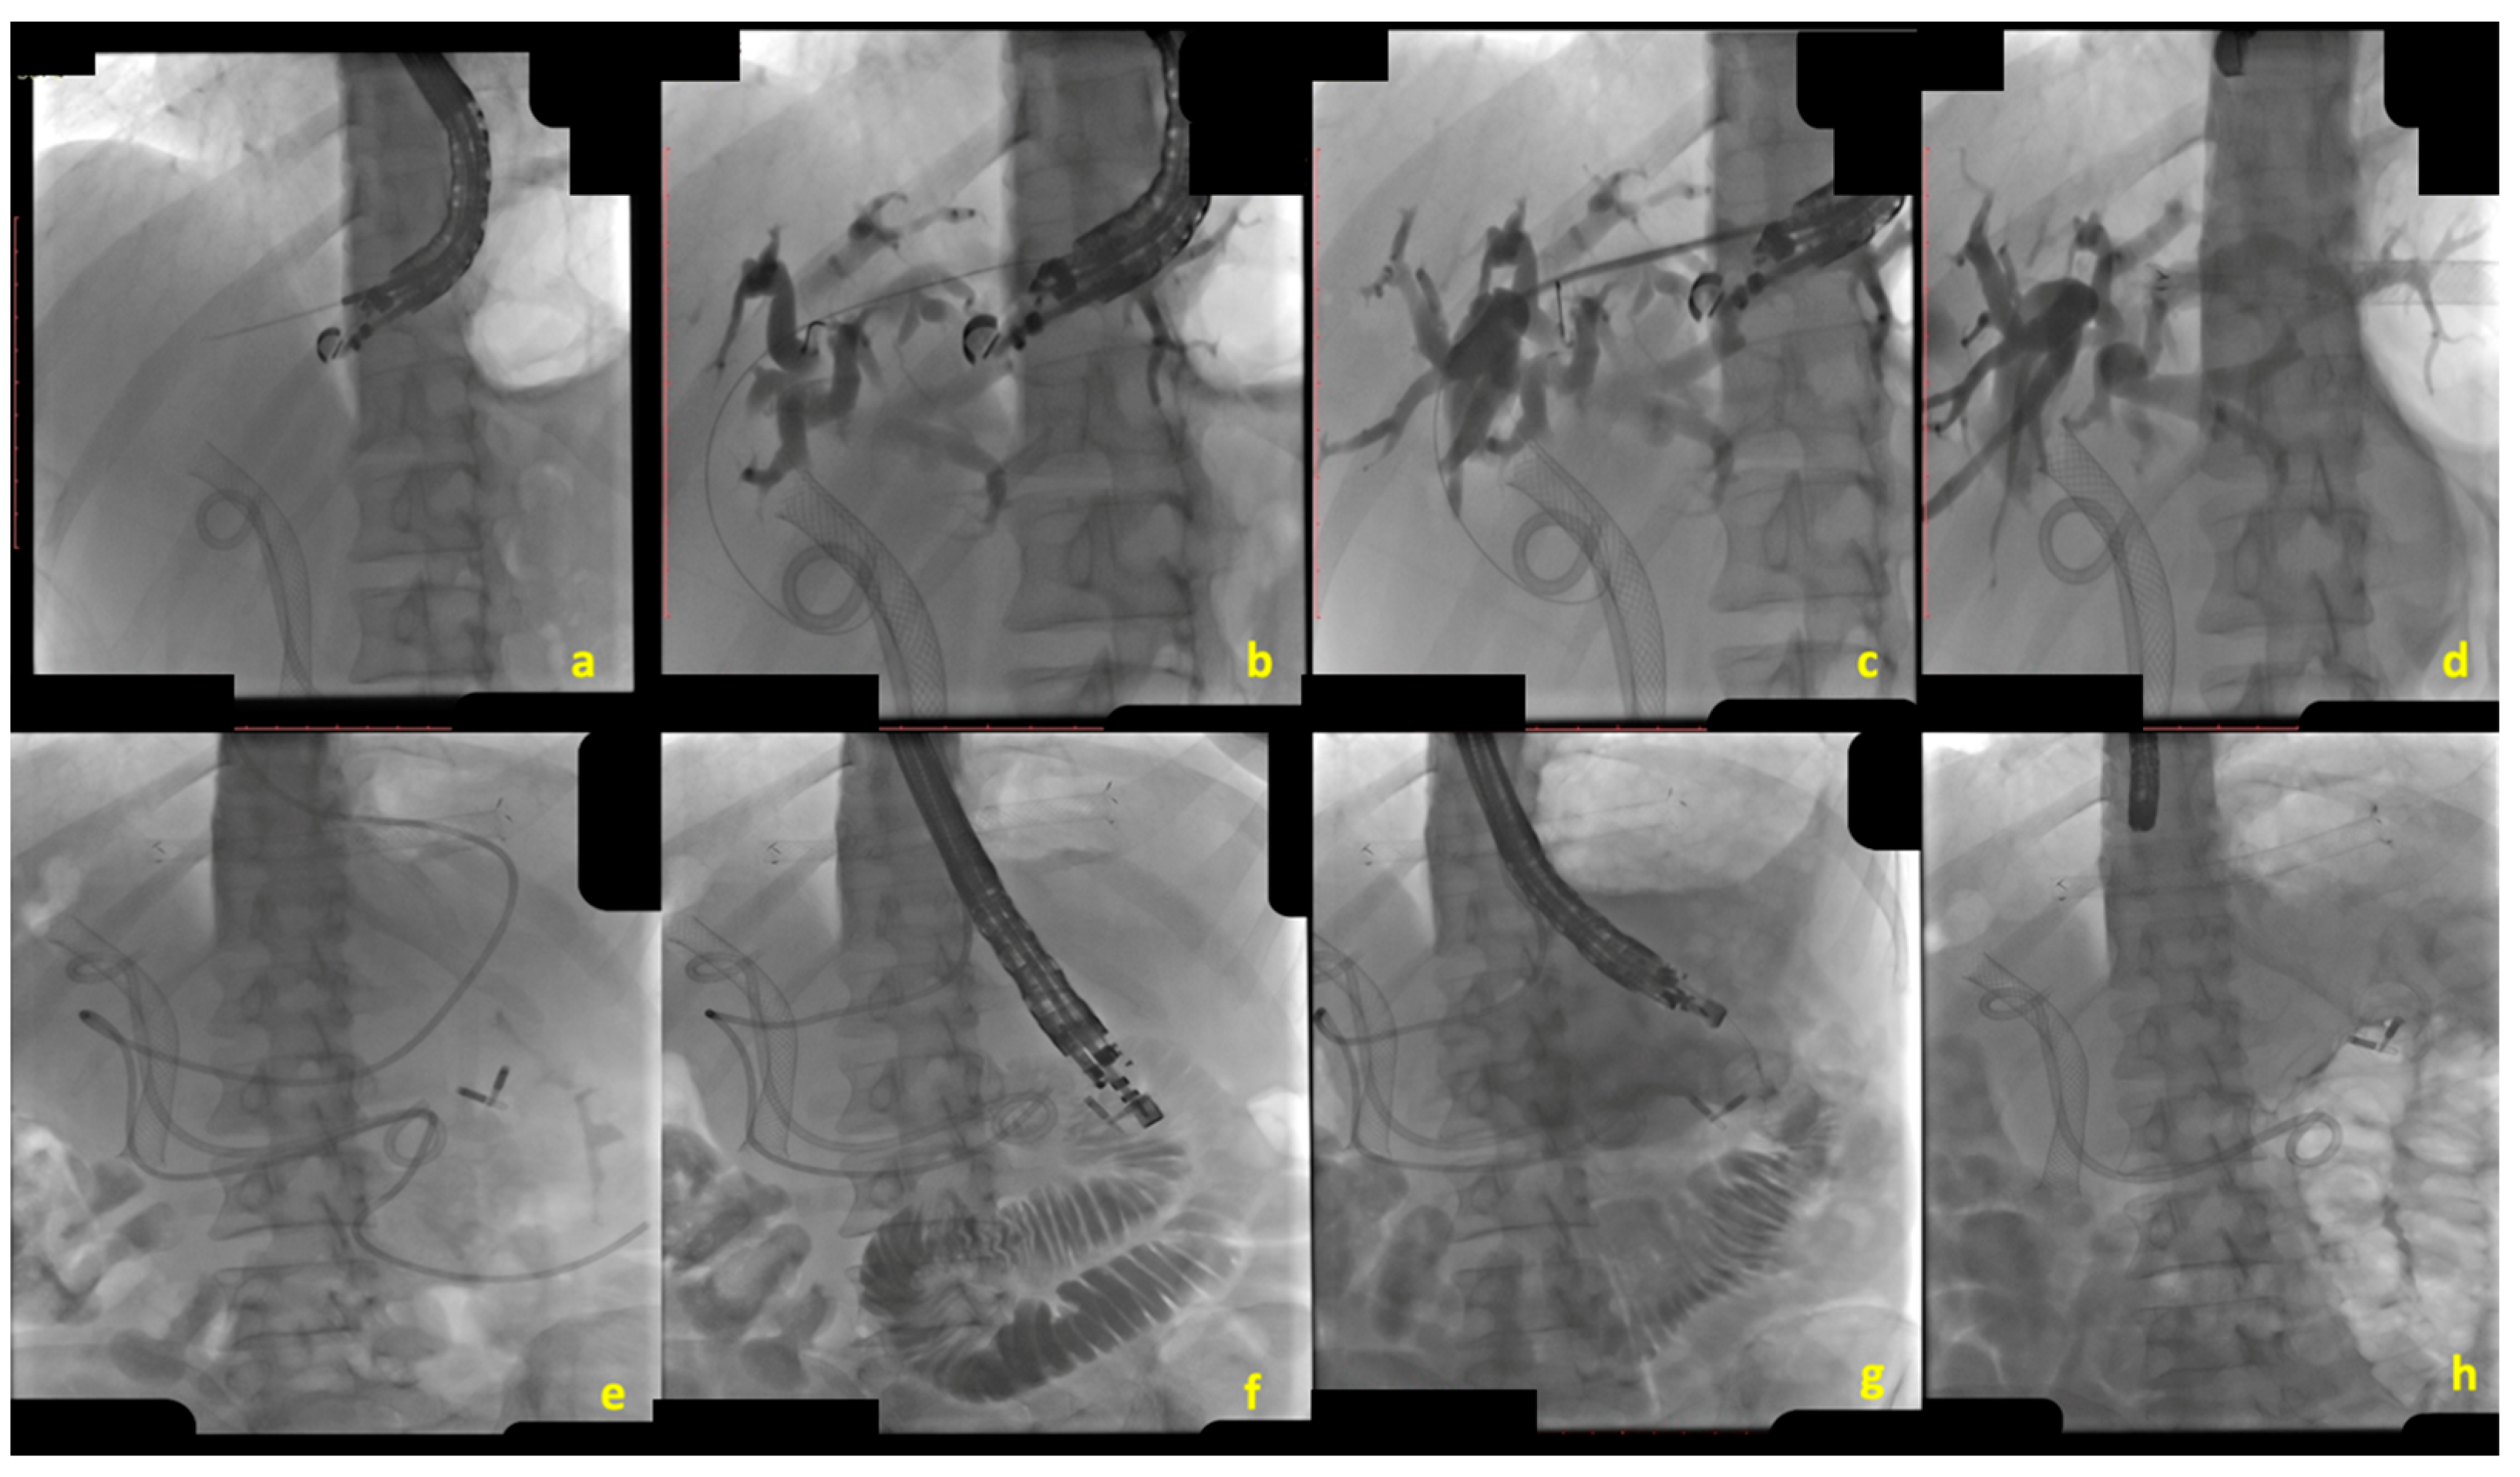

EUS-CDS consists of creating a bilio-digestive anastomosis between the common bile duct (CBD) and the duodenum [12] (Figure 1).

Under EUS guidance, from the duodenal bulb, the dilated CBD (>12 for expert operators, >15 mm for non-expert operators) was identified with the EUS scope in a “long” position, with the tip of the endoscope in the direction of the hepatic hilum [19]. At this stage, a bilio-digestive anastomosis is created by advancing an electrocautery-enhanced LAMS (ec-LAMS) directly into the CBD lumen under EUS guidance. While EUS-CDS can theoretically be performed without fluoroscopic assistance, in cases of a small-diameter CBD, the free-hand technique may be replaced with the over-the-wire technique [20]. This approach involves initially puncturing the CBD, preferably with a 19-gauge FNB needle, followed by the advancement of a guidewire into the CBD and performing a cholangiogram to confirm accurate access. The ec-LAMS catheter can then be advanced over the wire into the CBD, allowing for precise deployment of the LAMS. Indications from international societies (ESGE, ASGE) have evolved during the last couple of years. In 2022, the ESGE guidelines recommended EUS-CDS over EUS-HGS as the preferred technique for managing dMBO, citing a lower rate of adverse events (AEs) associated with EUS-CDS [13]. However, subsequent evidence has provided conflicting data regarding the safety profiles of these two procedures. A meta-analysis and systematic review by Yamazaki H et al., published in 2023, analyzed 18 studies encompassing 972 patients and found no significant difference in AEs between EUS-CDS and EUS-HGS (OR 1.39; 95% CI 1.00–1.93) [21]. In contrast, a newer meta-analysis by Rizqiansyah SY et al., published a year later, included 11 comparative studies (both controlled and uncontrolled) with a total of 537 patients and reported a significantly higher AE rate in the EUS-HGS group compared to the EUS-CDS group [22]. Furthermore, growing evidence showed that EUS-CDS may be associated with a risk of ascending cholangitis in the case of concomitant GOO [23,24]. In this view, the ASGE guideline suggested EUS-HGS over EUS-CDS in case of duodenal malignant infiltration, pre-existing ES, or GOO proximal to the pylorus [15].